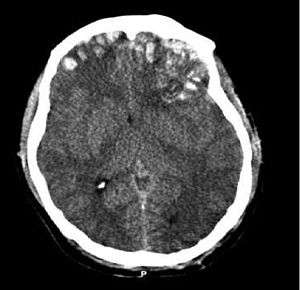

| CT scan showing cerebral contusions, hemorrhage within the hemispheres, subdural hematoma, and skull fractures[1] | |